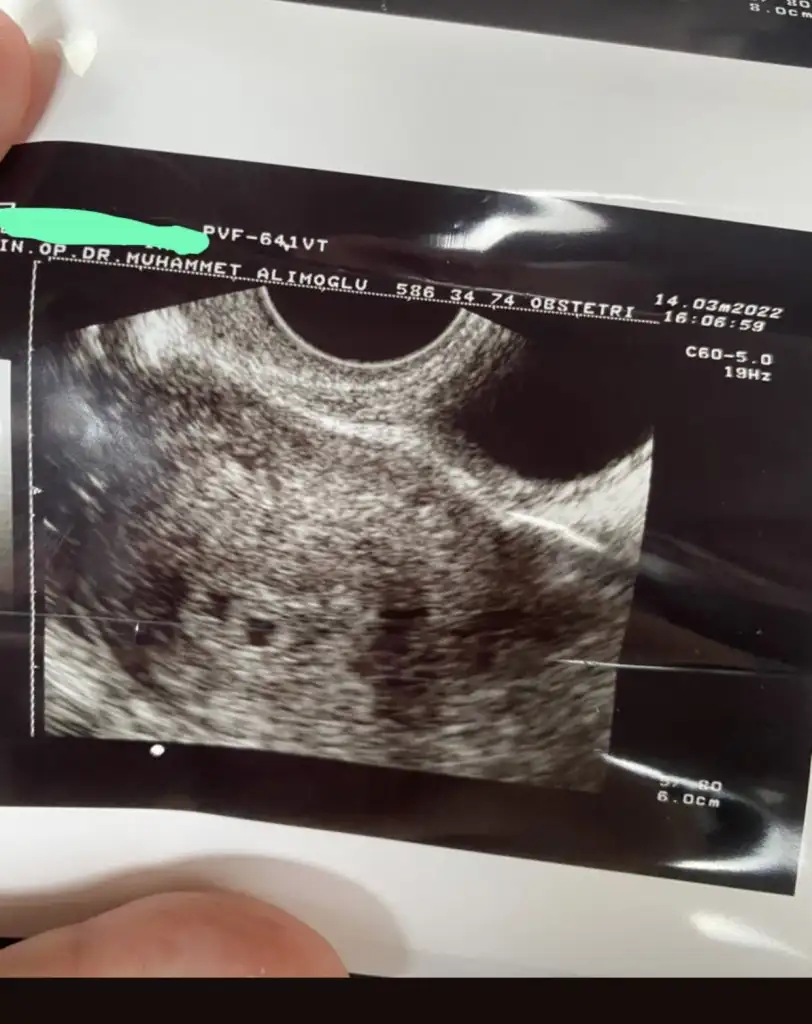

Eklentiler

• 2C19050E-4102-43F4-9CBD-75344C905CBE.webp

2C19050E-4102-43F4-9CBD-75344C905CBE.webp

34,8 KB · Görüntüleme: 81